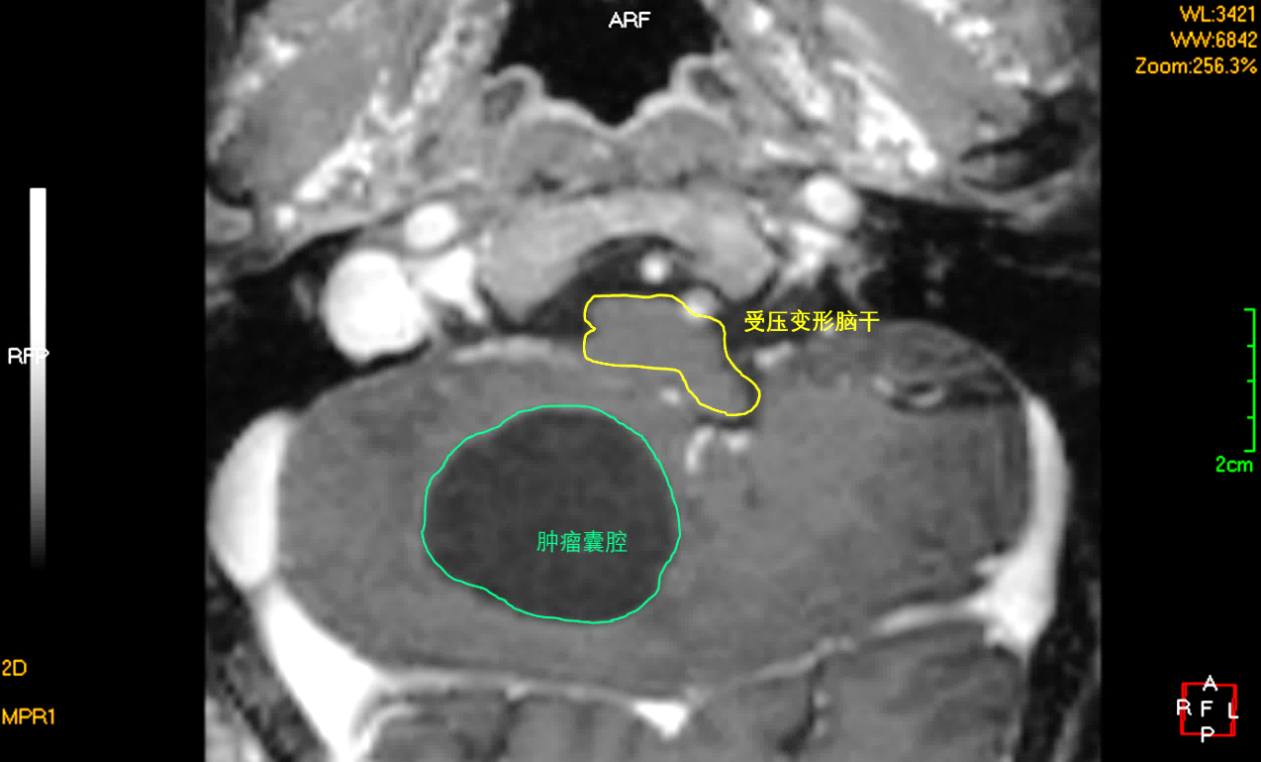

头颅MRI提示宋伯右侧小脑巨大囊实性占位,血管母细胞瘤可能性大,肿瘤实体部分不规则且靠近延髓,延髓受压变形严重,脑疝倾向,随时有生命危险。

术前头颅MRI示肿瘤巨大且呈囊实性改变